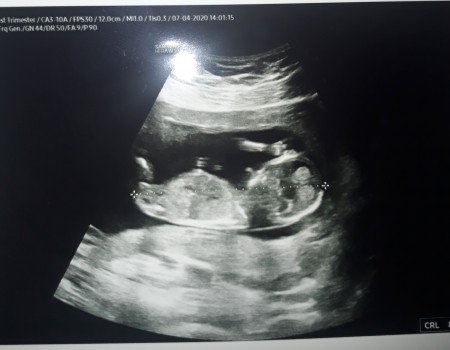

Sizce bu göbek kordonu mu

Gebelik haftası 17

Bana pipi gibi geldi canm zaten bi kac hafta sonra net belli olur:)erkek bu bebis

Öyle düşündüm ama çok büyük geldi gözüme acaba kordon mu dedi arkadaşlarım o yüzden çelişkşde kaldım

Erkek bence ama okdrda uzun gobek kordonudur

Bana kordon gibi geldi canim

Doktorunuz söylemedi mi cinsiyeti sanki alt taraftaki yumurtalık torbası

Pipi olması için bacak arasına doğru olması lazım bence bu daha yukarda kordon gibi yine de bilemiyorum canım :)

Bence göbek kordonu. Bizim kızında vardı ultrasonda çünkü:) o yüzden erkek sanmıştık dr kız deyince şok olduk

Kordon gibi seninki sanki kuzum bu kadar uzun büyük olamaz sanki benim burdada bak pipi gibi bişey var ama doktor kız dedi 14 haftaliktm orada

ultrason yakın çekimde o yüZden benm oğlumun da böyle duruyodu bi doğdu kücücük :)) kordon değil kordon öyle dikk durmuyor çünkü

Kordonada tbenzior pipiye de benziyor valla :) dr ne dedi.

Anaaaa ne kordonu pipi bu :D benimkide böyle açmıştı nerdeyse aynı fotosu var :D

Saglicakla kucaginiza alin insaallah..erkek annesi olucaksin.kordon deyil o..ultrasonda yakindan gorunduyu icin oyle